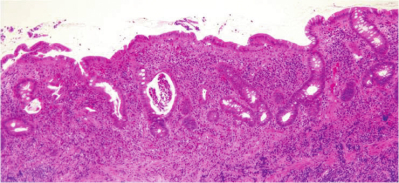

身長164cm、体重54kg。体温37.8℃。脈拍88/分、整。血圧120/60mmHg。眼瞼結膜は軽度貧血様である。内視鏡検査では結腸に多発性のびらんと潰瘍とを認める。採取された結腸粘膜生検組織のH-E染色標本を別に示す。

本標本に認められる所見はどれか。3つ選べ。